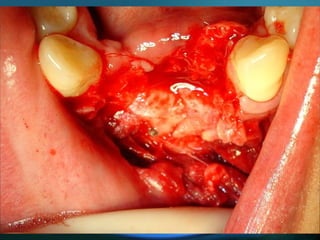

Eliminación de focos sépticos en bloque en paciente con osteitis

mandibular crónica

Osteitis

Imagen microscópica de osteitis, inicialmente existe una etapa de

osteoclastosis seguida por regeneración. No siempre el hueso

regenera en su totalidad y sigue el curso de cualquier inflamación

dejando un area de tejido fibroso que con el tiempo puede

calcificarse (hueso denso)

Manejo con antibióticos obligado

Revisión periódica